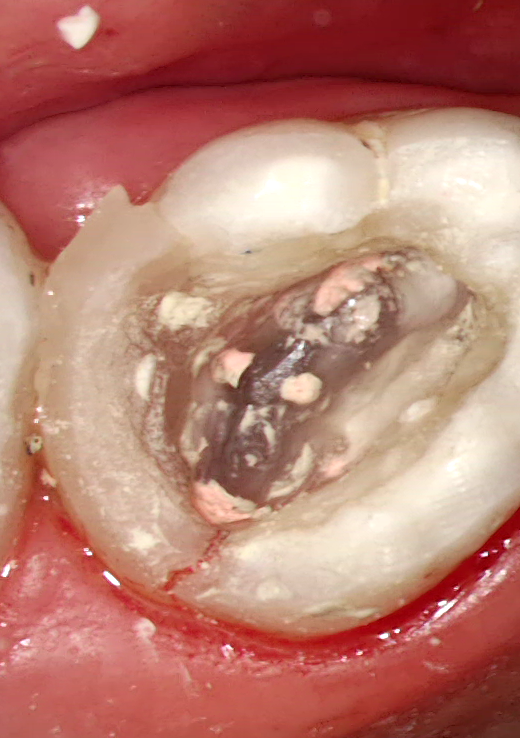

Leggyakoribb orvosi hiba lehetőségek:

Álút képződés

Perforáció (fenti kép)

Túltömés

Tű-törése (fent)

Feltáratlan gyökércsatorna (fent)